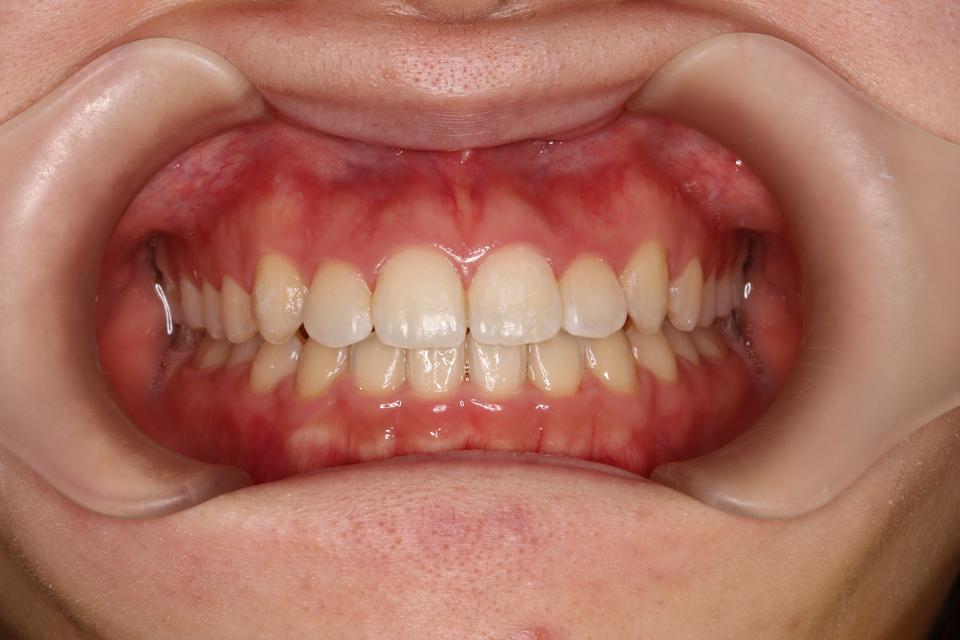

矯正治療後

上下の歯にワイヤー(マルチブラケット装置)をつけて治療しました。

きれいに並びきるために歯のやすりがけ(IPR)も行っています。

歯並びを並べる治療は終わり、

取り外しのできる装置をはめることで後戻りの防止をして

定期的にチェックをしています。

| 矯正治療期間 | 11か月・16回(保定装置装着まで※保定観察を除きます) |

| 抜歯の有無 | なし |

| 治療費 | 1055000円(検査/診断/施術料・保定装置代を含む※保定期間中は保定観察料金が別途必要です(3000円/回) ) |